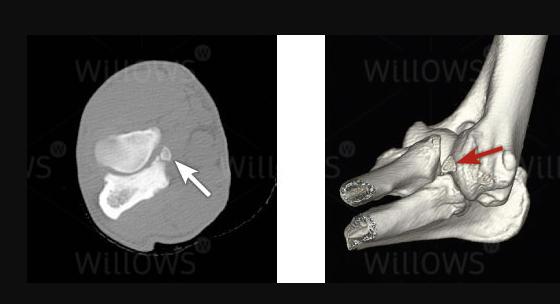

如若保守治疗没有效果,或者小狗自身存在极大的问题,关节内存在多块软骨碎片,便需要进行手术康复。

通常兽医会采取这类手术方式较多,因为主要常规操作是通过关节镜手术来完成,可以将肘关节内部全部碎片一一清除。

总结:无论兽医是使用哪一种手术方式,我们作为饲主都需要知道,主要目的在于消灭任何有缺陷的病变区域。

软骨病站立不起来怎么回事,小狗狗髋关节有问题不会站立

兽医口中所说的“关节碎片”